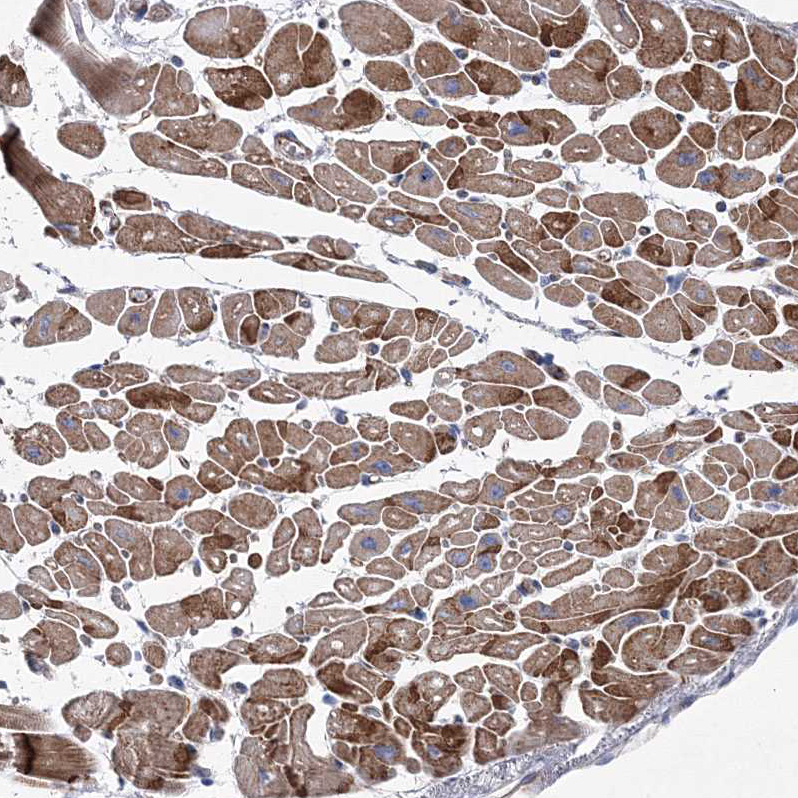

Immunohistochemical staining of human testis shows moderate cytoplasmic positivity in Leydig cells.